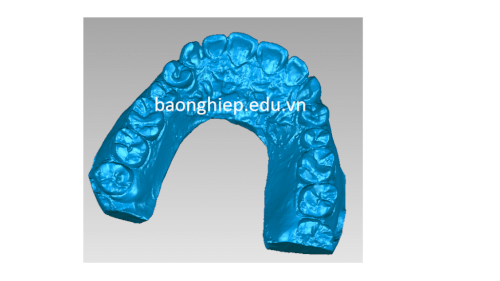

- Cống nghệ scan3d đáp ứng nhu cầu phục vụ trong ngành nha khoa chỉnh hình răng

scan3d chỉnh hình răng hàm trên